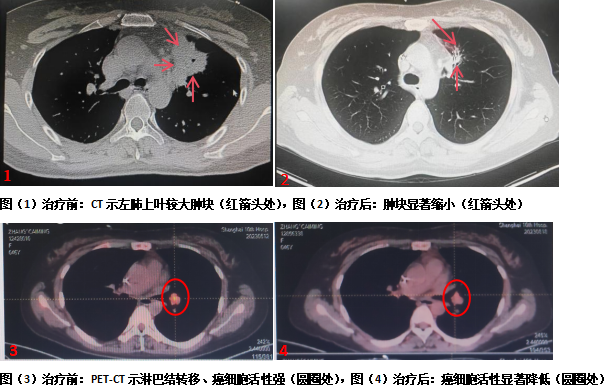

一年前,张女士感到背部时不时疼痛,以为是不小心拉伤了背部肌肉,但检查结果却让她和家人大吃一惊——“左肺上叶前段肿瘤伴局部淋巴结和远处骨转移”。

一次偶然的机会,张女士得知,上海市第十人民医院范理宏教授领衔的国家级中西医结合旗舰科室团队,在肺癌治疗领域形成了独具特色的优势,便慕名前来。在经过认真细致的病情分析,范理宏认为该患者没有可匹配的常用靶向药物,选择什么样的高效低毒治疗方式控制病灶生长,是治疗的难点。

消融治疗在局麻下进行,在CT扫描定位及监测下,将冷冻治疗针精准穿刺置入瘤体,开启冷冻装置后,快速“冻死”了大块癌灶。整个消融治疗过程患者几乎无痛感,消融治疗顺利完成。消融术后,范理宏及其团队为患者张女士制定了白蛋白紫杉醇化疗、免疫药治疗、放疗、抗肿瘤血管生成治疗、新靶点靶向治疗及全程中医药修复线粒体治疗等综合治疗,患者张女士后续的抗肿瘤过程耐受性良好,生活质量较前显著提高。